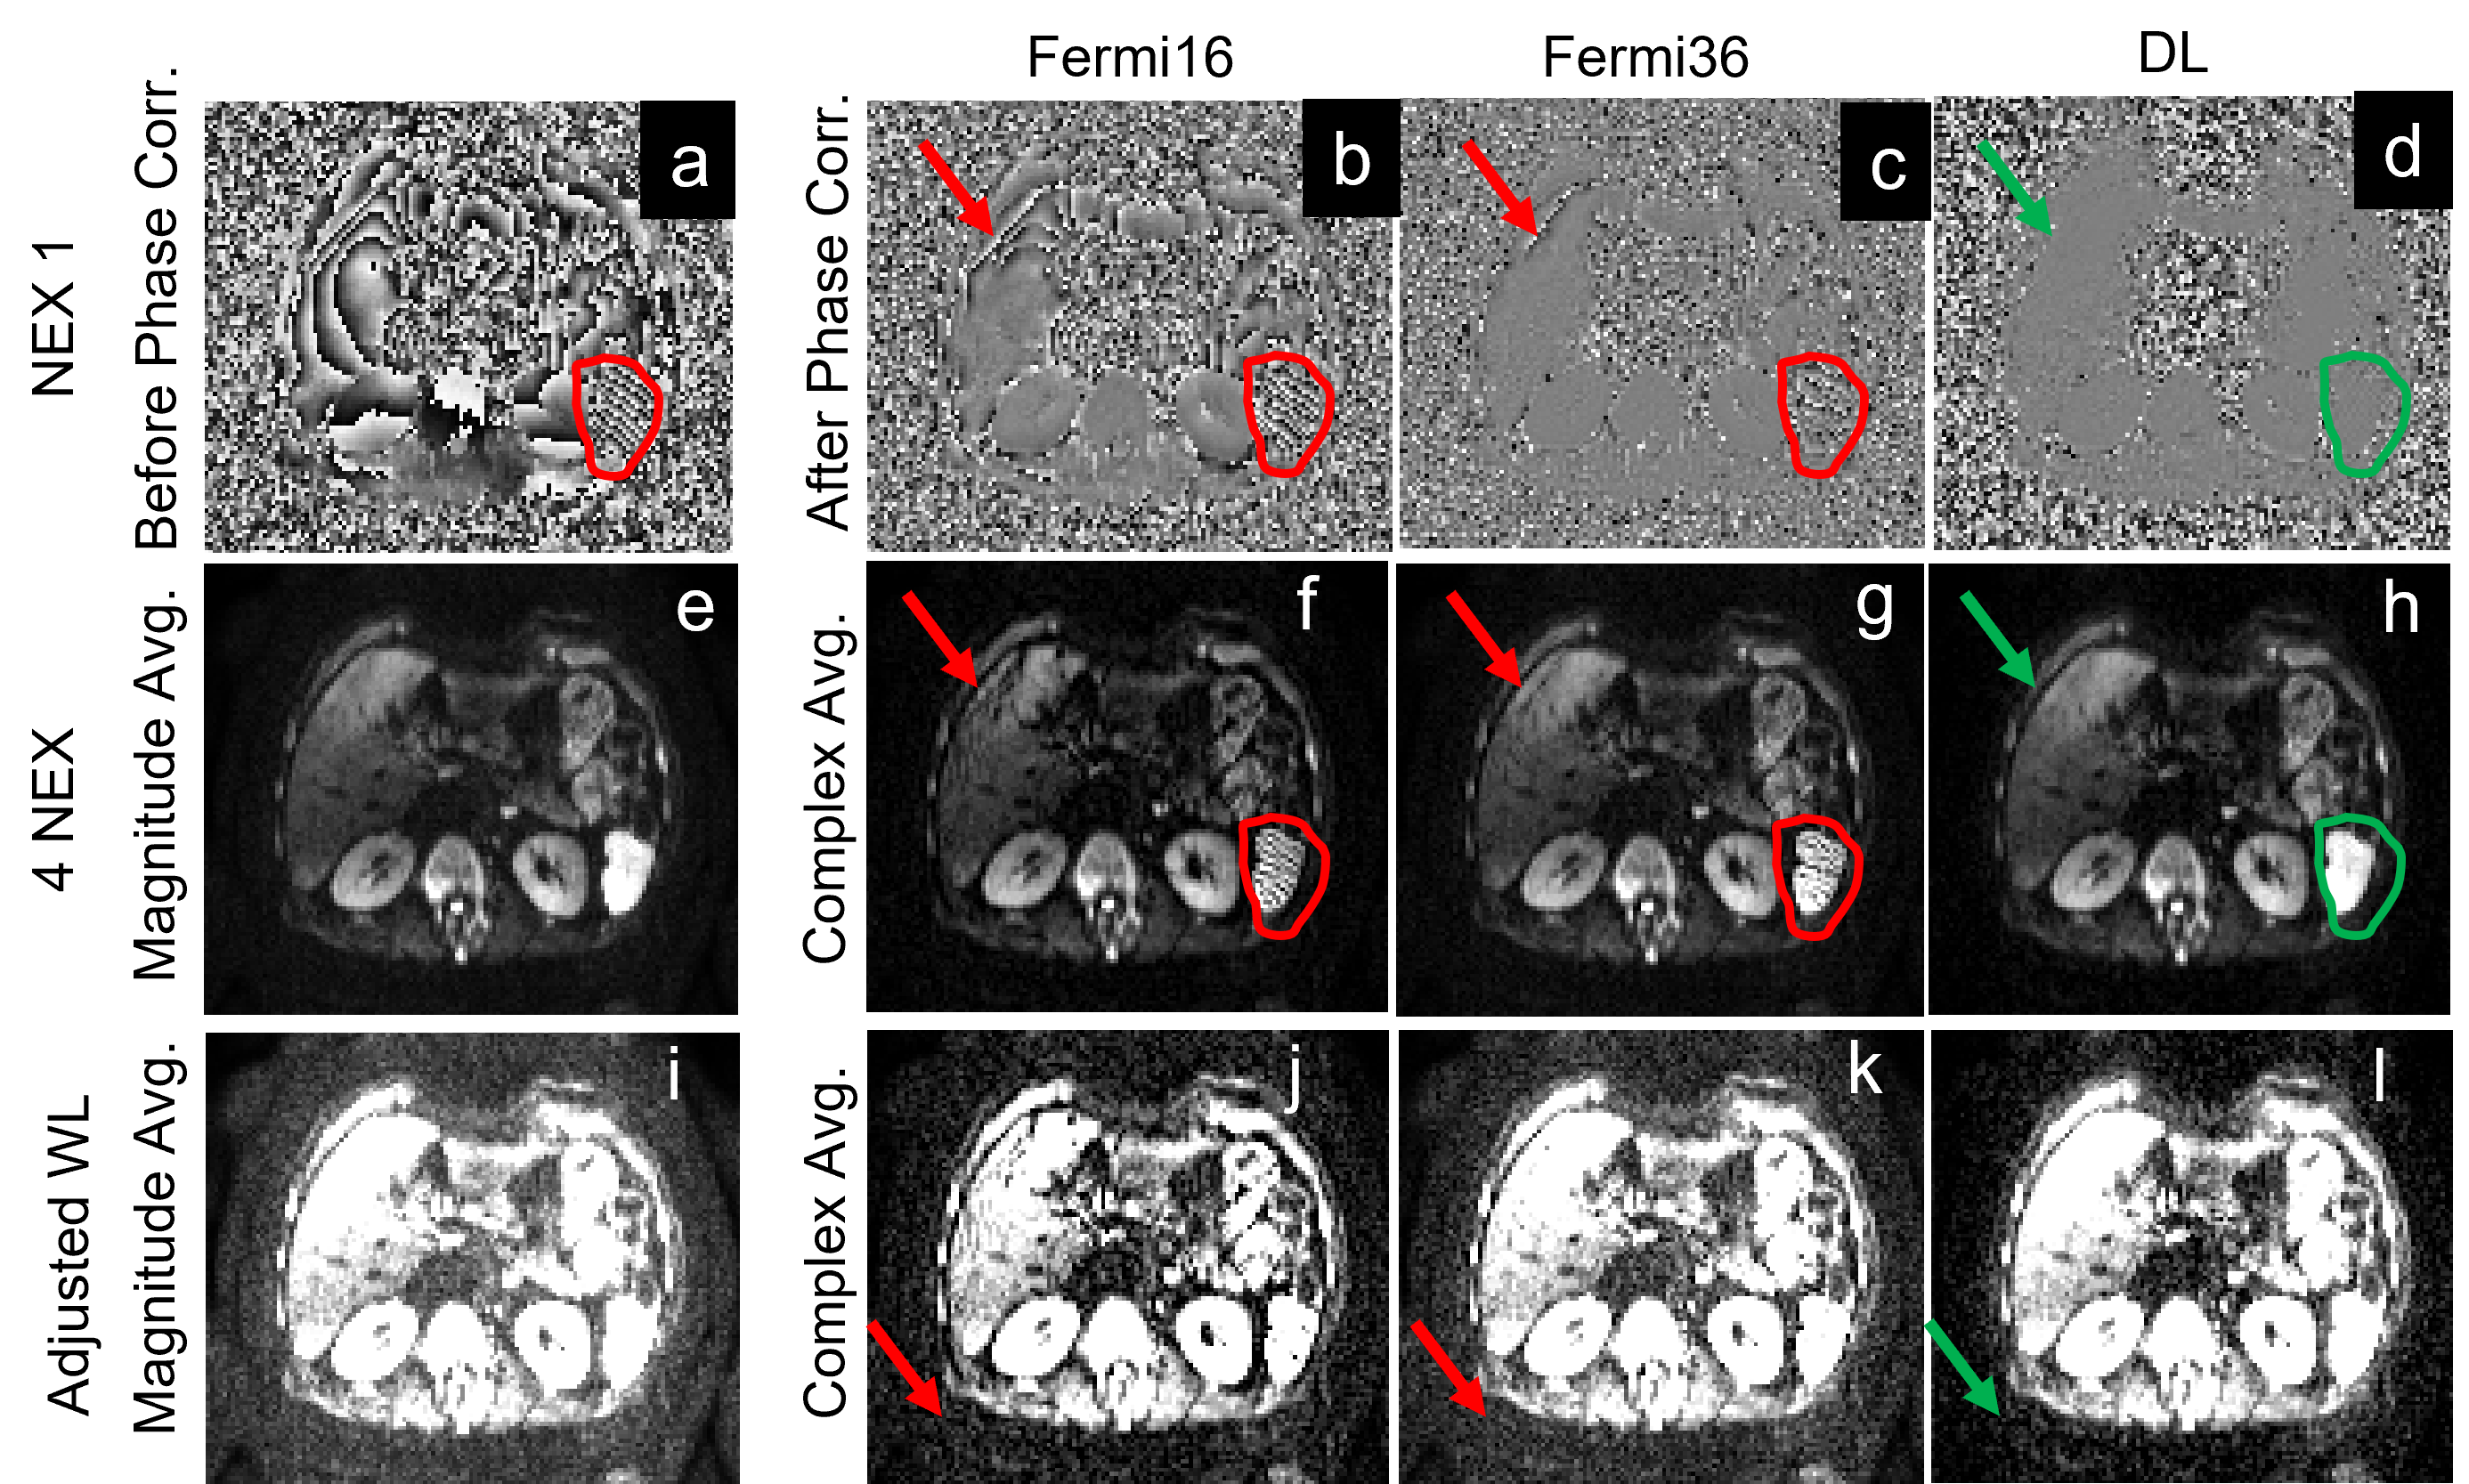

Figure 2 shows the brain DW images at b=2500. Phase correction with a large kernel (Fermi16) minimized the signal bias and reduced background noise in the averaged image, but left more signal in the imaginary channel (Figure 2g). Reducing the kernel size (Fermi36) reduced the signal in the imaginary channel but resulted in increased signal bias and higher noise floor (Figure 2e). DL-based phase correction achieved minimal signal bias and noise floor while preserving signal in the real channel (Figure 2f, 2i).

Figure 2. Complex averaging using filter-based phase correction and DL-based phase correction with b=2500 brain images. (a-c) are the real images; (d-f) are the same images but with a different window level to show the background noise; (g-i) are the imaginary images. Compared to a small kernel (Fermi36), a large kernel (Fermi16) could reduce the signal bias, resulting in a lower noise floor (d vs e). However, more signal was also left in the imaginary channel (g vs h). In contrast, DL-based phase correction showed lowest noise floor and minimum loss of signals.